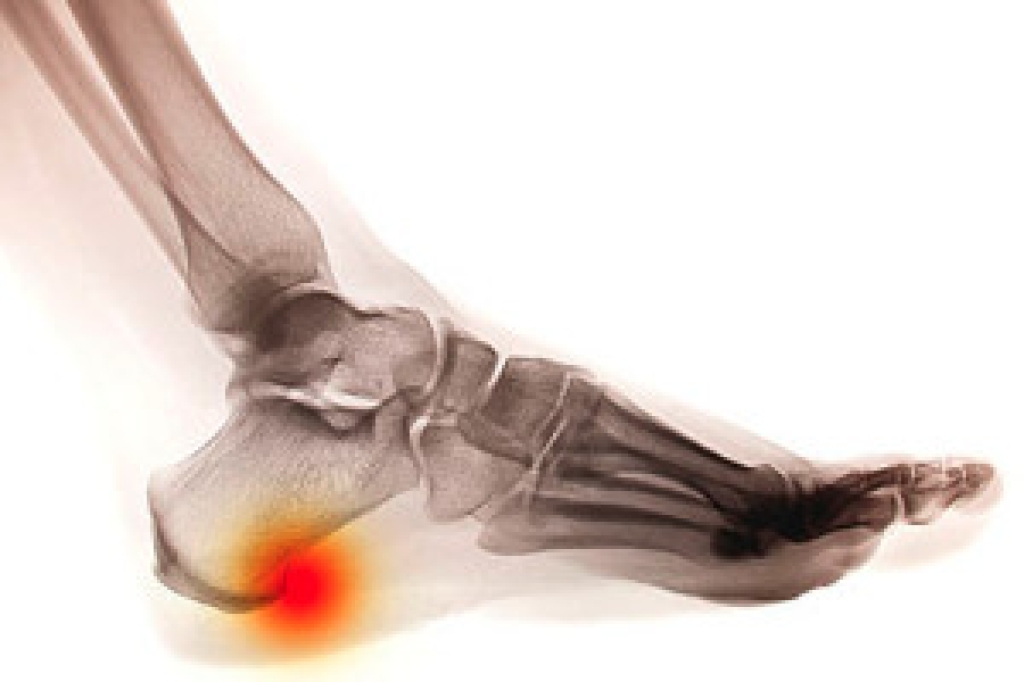

Diabetic foot is a condition that can require a hospital stay for some diabetic patients. It is a condition that may cause the patient to lose feeling in their feet, which can make it difficult to feel a cut or a bruise. It occurs as a result of elevated blood sugar levels. It is beneficial to control the amount of sugar that is ingested, and this is often helpful in keeping glucose levels within a normal range. Additionally, many patients find their feet feel better when they are gently washed and dried, and trimming the toenails correctly may help to avoid cuts on the toes. It is important to incorporate gentle exercise into your daily routine, as this may help to improve circulation and overall health. If you have diabetes, it is strongly suggested that you are under the care of a podiatrist who can help you to properly manage any foot-related problems that may arise because of this condition.

Diabetes affects millions of people every year. The condition can damage blood vessels in many parts of the body, especially the feet. Because of this, taking care of your feet is essential if you have diabetes, and having a podiatrist help monitor your foot health is highly recommended.